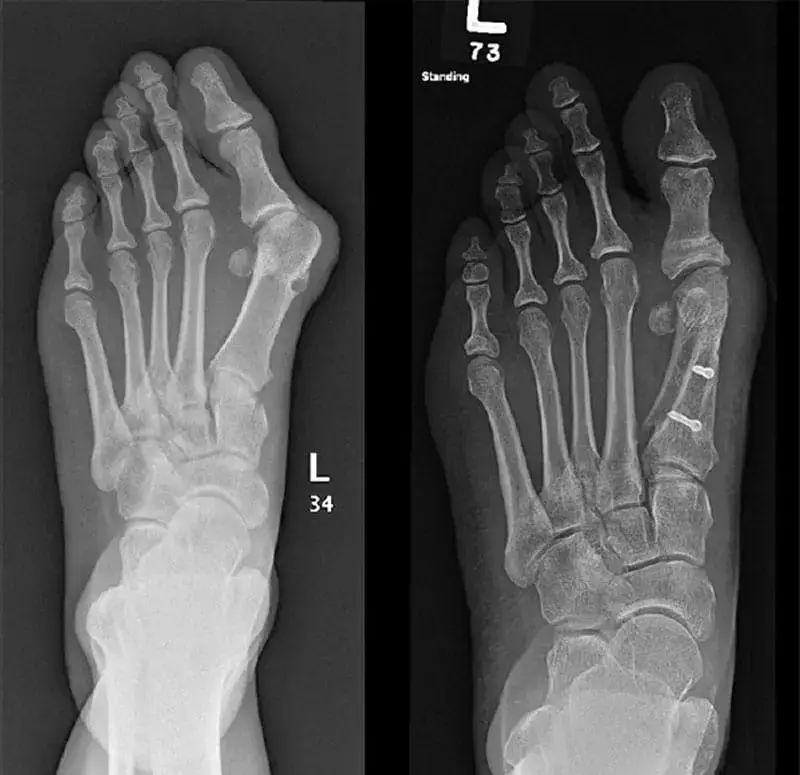

Czy to nie wszystko przed i po?

Z wiekiem rozwinęła się u mnie deformacja palucha koślawego stopy. Na początku guzek tylko rósł, a potem zaczęły się straszne bóle. To samo stało się z moim ojcem, bardzo cierpiał. Poszedłem do lekarza i powiedział mi, że tylko operacja może mi pomóc. Ale moja żona znalazła opinie o ReumoMax Complex na kilku stronach i zdecydowała się zamówić. Zacząłem go używać i w ciągu trzech dni mój ból zniknął. W ciągu dwóch tygodni kostka zniknęła! I mogłem normalnie chodzić! Spójrzcie na moje wyniki!

Już kupione. Niska cena, szybka dostawa. Zobaczcie mój wynik. Zdjęcia przed/po